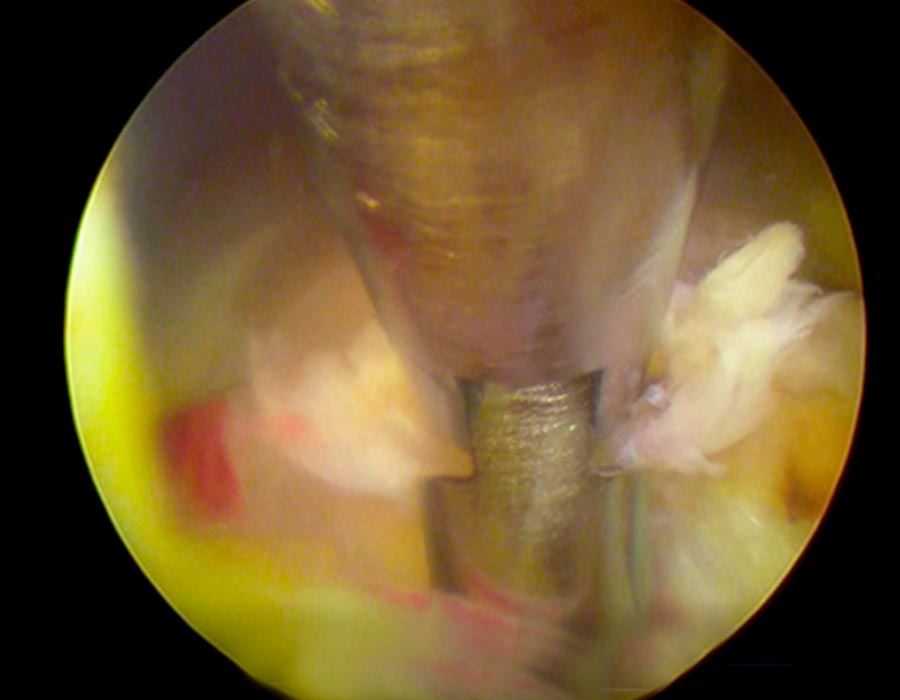

Se realiza una incisión de 3mm en la parte correspondiente de la espalda y, sin producir ningún daño en los tejidois, accedemos al área afectada, directamente al canal de la vértebra lumbar.

Tras localizar la zona de trabajo, suavizamos la hernia y procedemos a su retirada y al posterior sellado tanto del disco como del anillo donde ha salido la hernia para evitar futuras fugas.

Comprobamos adecuadamente que todas las estructuras neurológicas han quedado descomprimidas y liberadas y gozan de buen riego bascular.